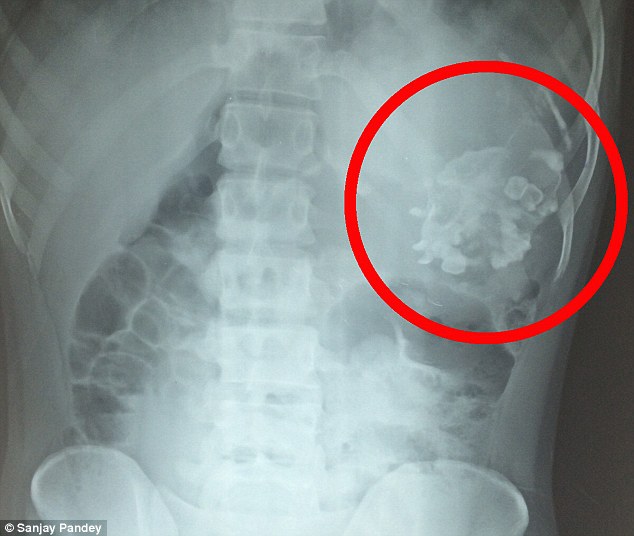

Narendra Kumar, sem er 18 ára gamall, var fluttur í hasti á Swaropp spítalann í indverska bænum Uttar Pradesh, sem er staðsettur í norðurhluta Indlands sökum þrálátra magaverkja sem ullu þrálátu þyngdartapi, krónískum uppköstum og gífurlegum sársauka. Í fyrstu var ekki vitað hvað olli verkjunum, en eftir talsverðar rannsóknir leiddi sneiðmyndataka og röntgenmyndir í ljós að drengurinn gekk með æxli í maganum, sem var 20 cm í þvermál og vó 2.5 kíló að þyngd.

Æxlið reyndist vera fósturvísir að vansköpuðum tvíburabróður Narendra og samanstóð af beinmassa, talsverðum hárvexti og risavöxnum tönnum, sem höfðu þroskast afbrigðilega í maga unga mannsins.

Um gífurlega sjaldgæft heilkenni er að ræða sem í læknisfræðinni nefnist fetus in fetu og, en slíkt gerist þegar eitt fóstur gleypir systkini sitt meðan á meðgöngu stendur. Sá tvíburinn sem er gleyptur af hinum, nærist á þeim næringarefnum sem hýsillinn veitir, en afmyndaða fóstrið hreiðrar venjulega um sig í maga hýsilsins, þó einnig séu dæmi þess að slíkir tvíburar hafi vaxið í höfuðkúpu systkina sinna og jafnvel í náranum.